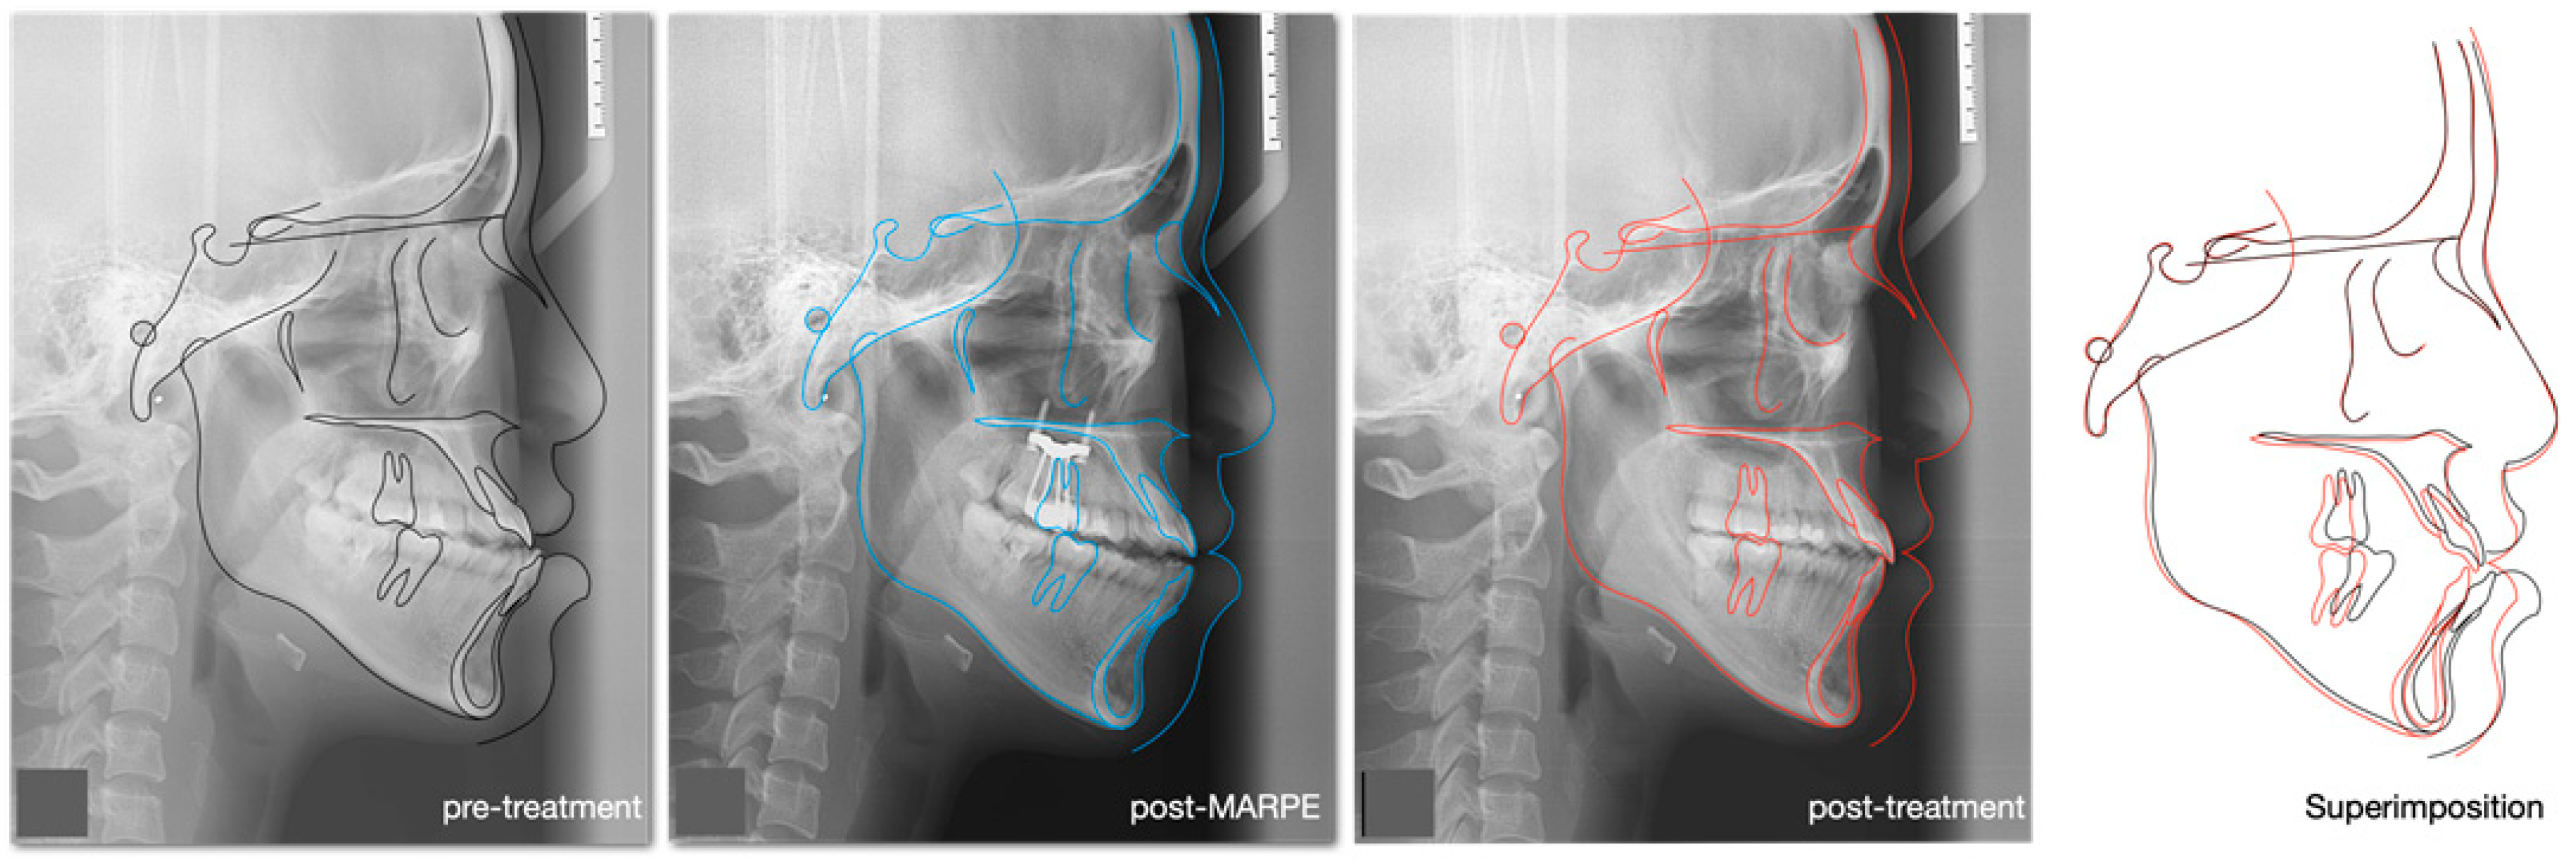

| SNA | 81° ± 3° | 81° | 81.5° | 81° |

| SNB | 78° ± 3° | 83.5° | 81.5° | 81.5° |

| ANB | 3° ± 2° | −2.5° | 0° | −0.5° |

| Vertical Skeletal Relationships | ||||

| Maxillary inclination (S-N/ANS-PNS) | 8° ± 3° | 8° | 8° | 8° |

| MMPA | 27° ± 3° | 28° | 31° | 30° |

| LFH % | 55% ± 2% | 58.5% | 58.7% | 58.6% |

| Dento-Basal Relationships | ||||

| Upper incisor to Max. plane | 108° ± 6° | 126.5° | 126.5° | 126° |

| Lower incisor to Mand. Plane | 93° ± 6° | 94° | 92° | 83° |

| Lower incisor to A-Po line | 1 ± 1 mm | +12.5 mm | +8 mm | +5 mm |

| Inter-incisal angle | 133° ± 10° | 111° | 110° | 120° |

| E-Line | ||||

| Upper lip-E line | −2 ± 2 mm | −3 mm | −2 mm | −3 mm |

| Lower lip-E line | 0 ± 2 mm | +4 mm | +3 mm | −1 mm |